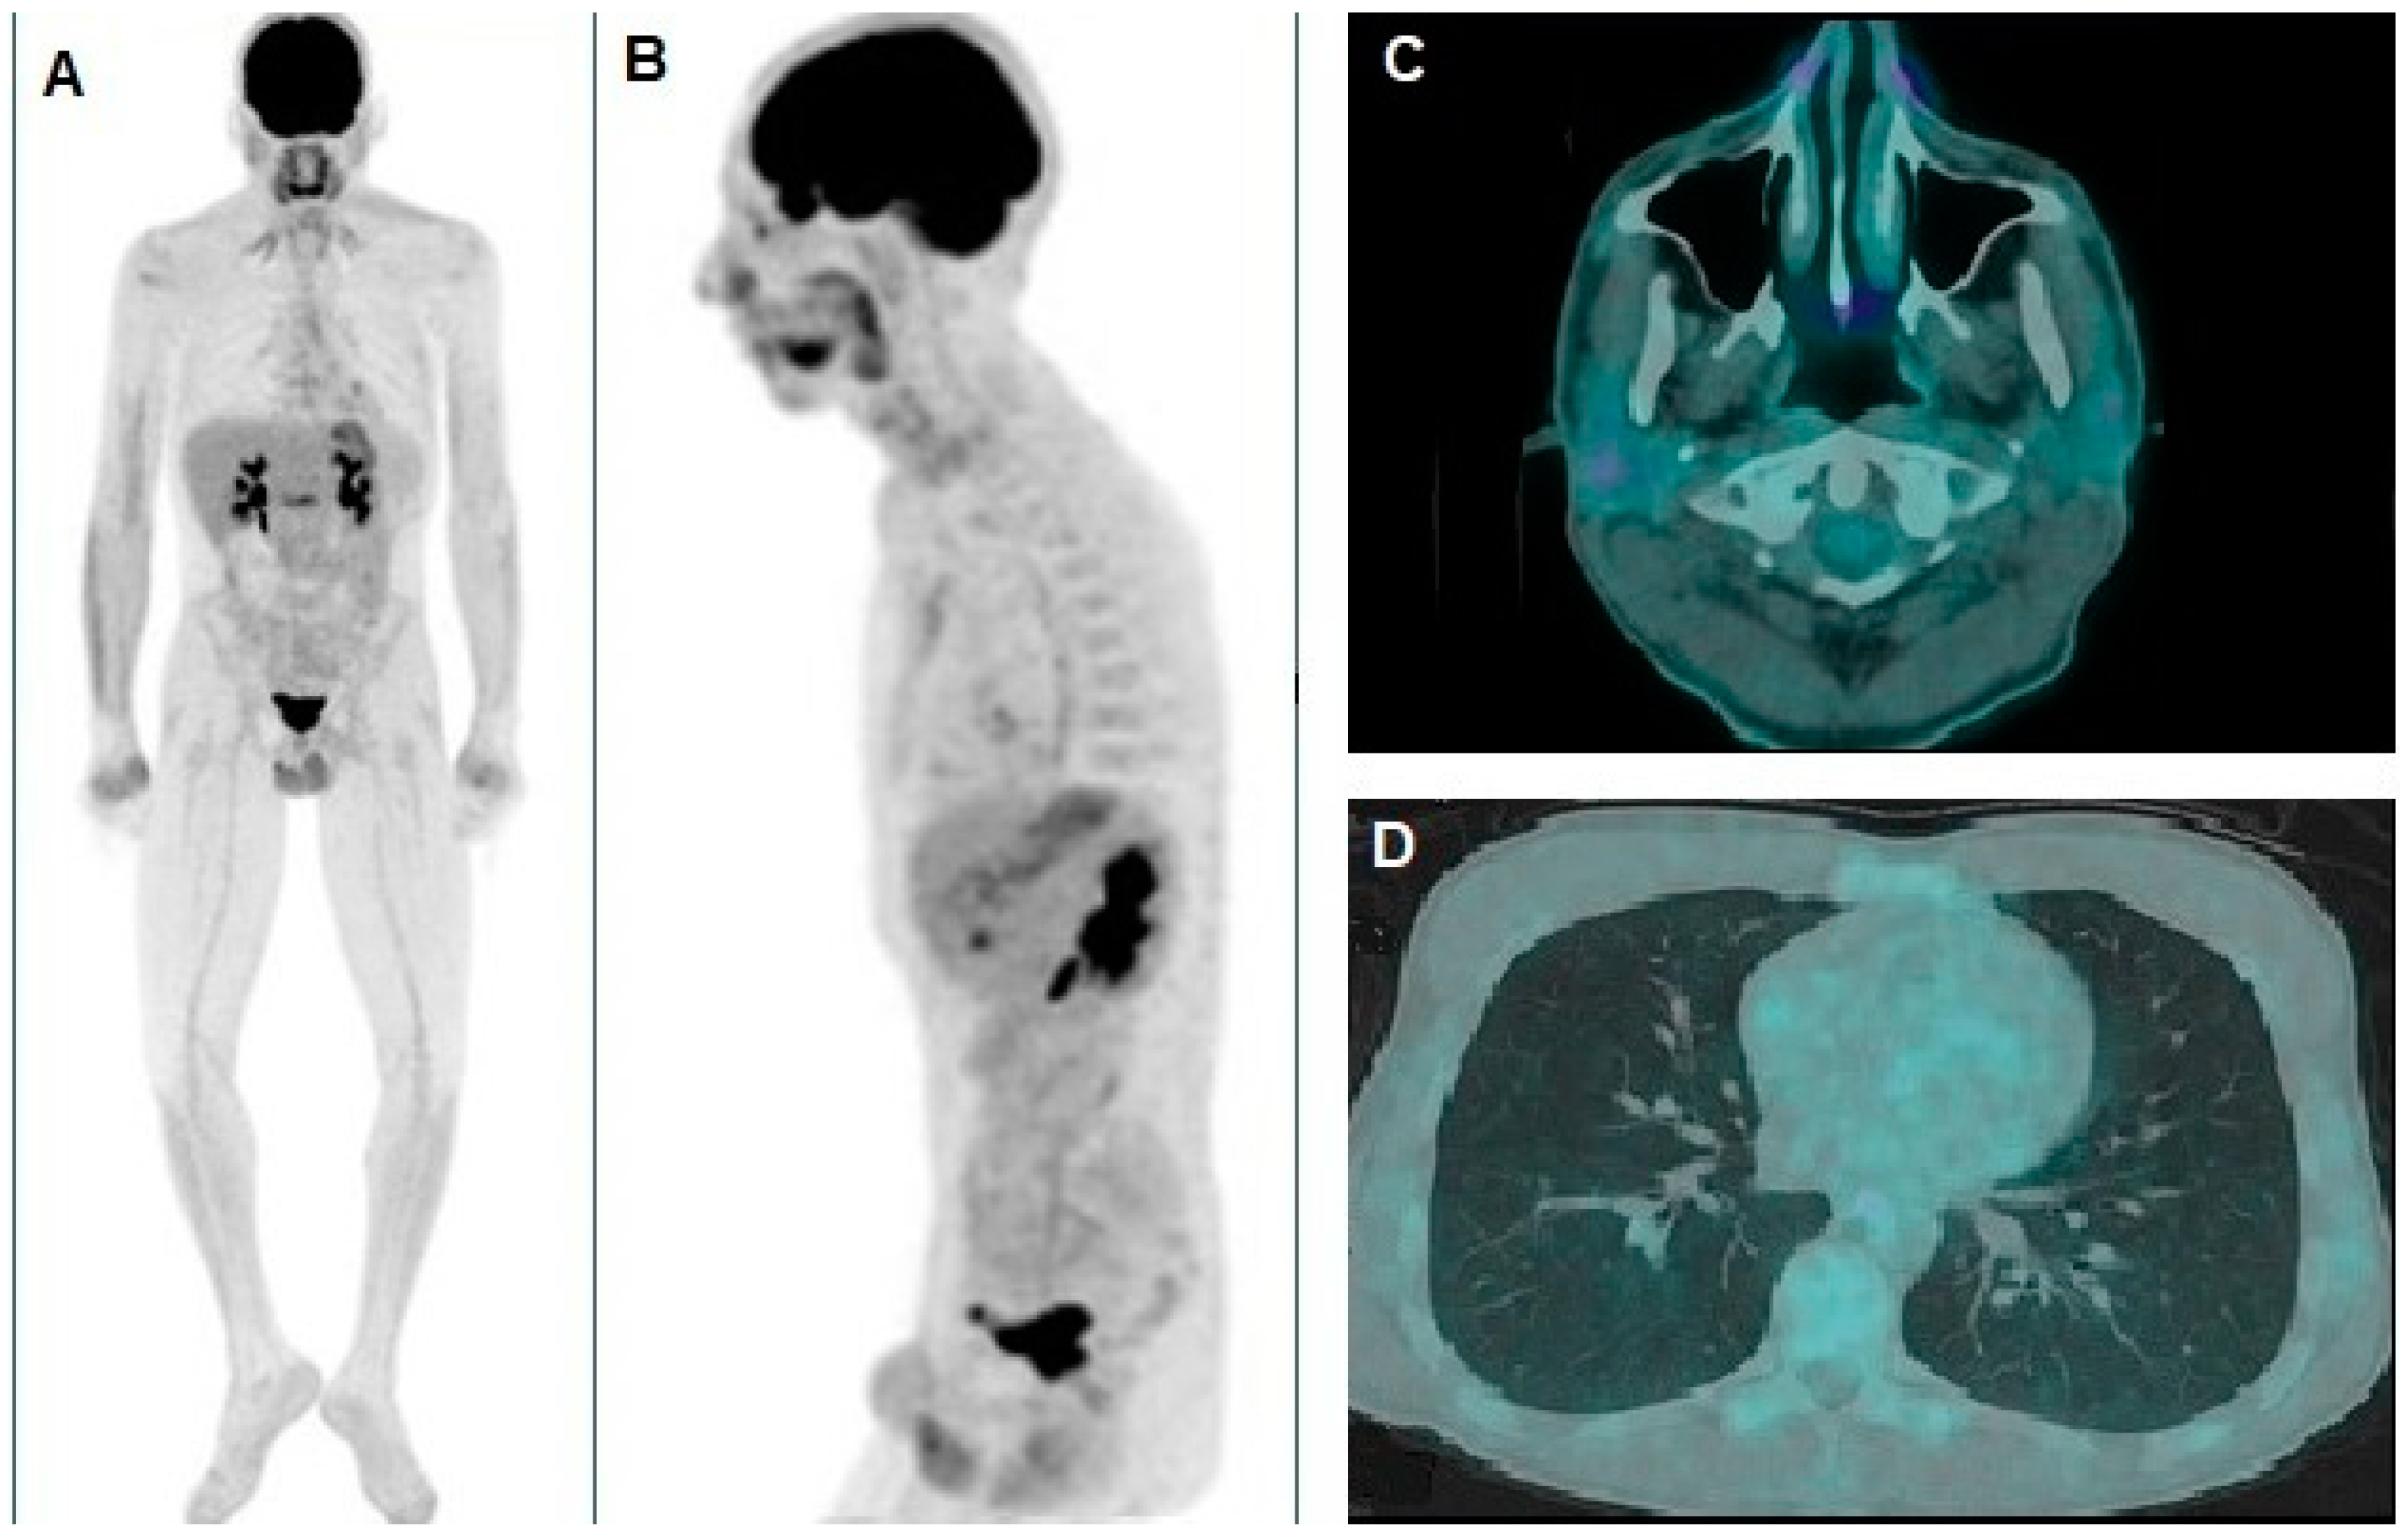

A Rare Case of Xeroderma Pigmentosum: Nivolumab Treatment for Three Cutaneous Malignancies with Clinical and Metabolic Imaging Correlation

Proietti, I.; Pirisino, R.; Azzella, G.; Coppolelli, V.; Greco, M.E.; Casciani, E.; Potenza, C.; Filippi, L. A Rare Case of Xeroderma Pigmentosum: Nivolumab Treatment for Three Cutaneous Malignancies with Clinical and Metabolic Imaging Correlation. Diagnostics 2025, 15, 979. https://doi.org/10.3390/diagnostics15080979